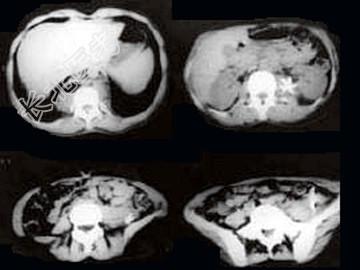

- 单项选择题女,34岁, 咳嗽,腰背疼痛二年, CT检查如图,最可能的诊断是 ( )

A、结核性脓肿

B、囊肿

C、淋巴管瘤

D、卵巢囊肿

E、卵巢囊腺瘤